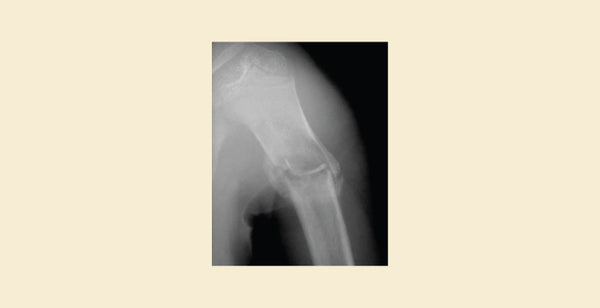

- X-rays show a single, well-defined, fluid-filled cavity (unicameral, meaning "one chamber") in the bone's middle section (metaphysis). The surrounding bone may have a narrow ring of reactive bone development.

- X-rays reveal a more expansive, multi-chambered (multicameral) fluid-filled cavity with a thinner, occasionally bulging, bony exterior. May be eccentric (off-center) within the bone.